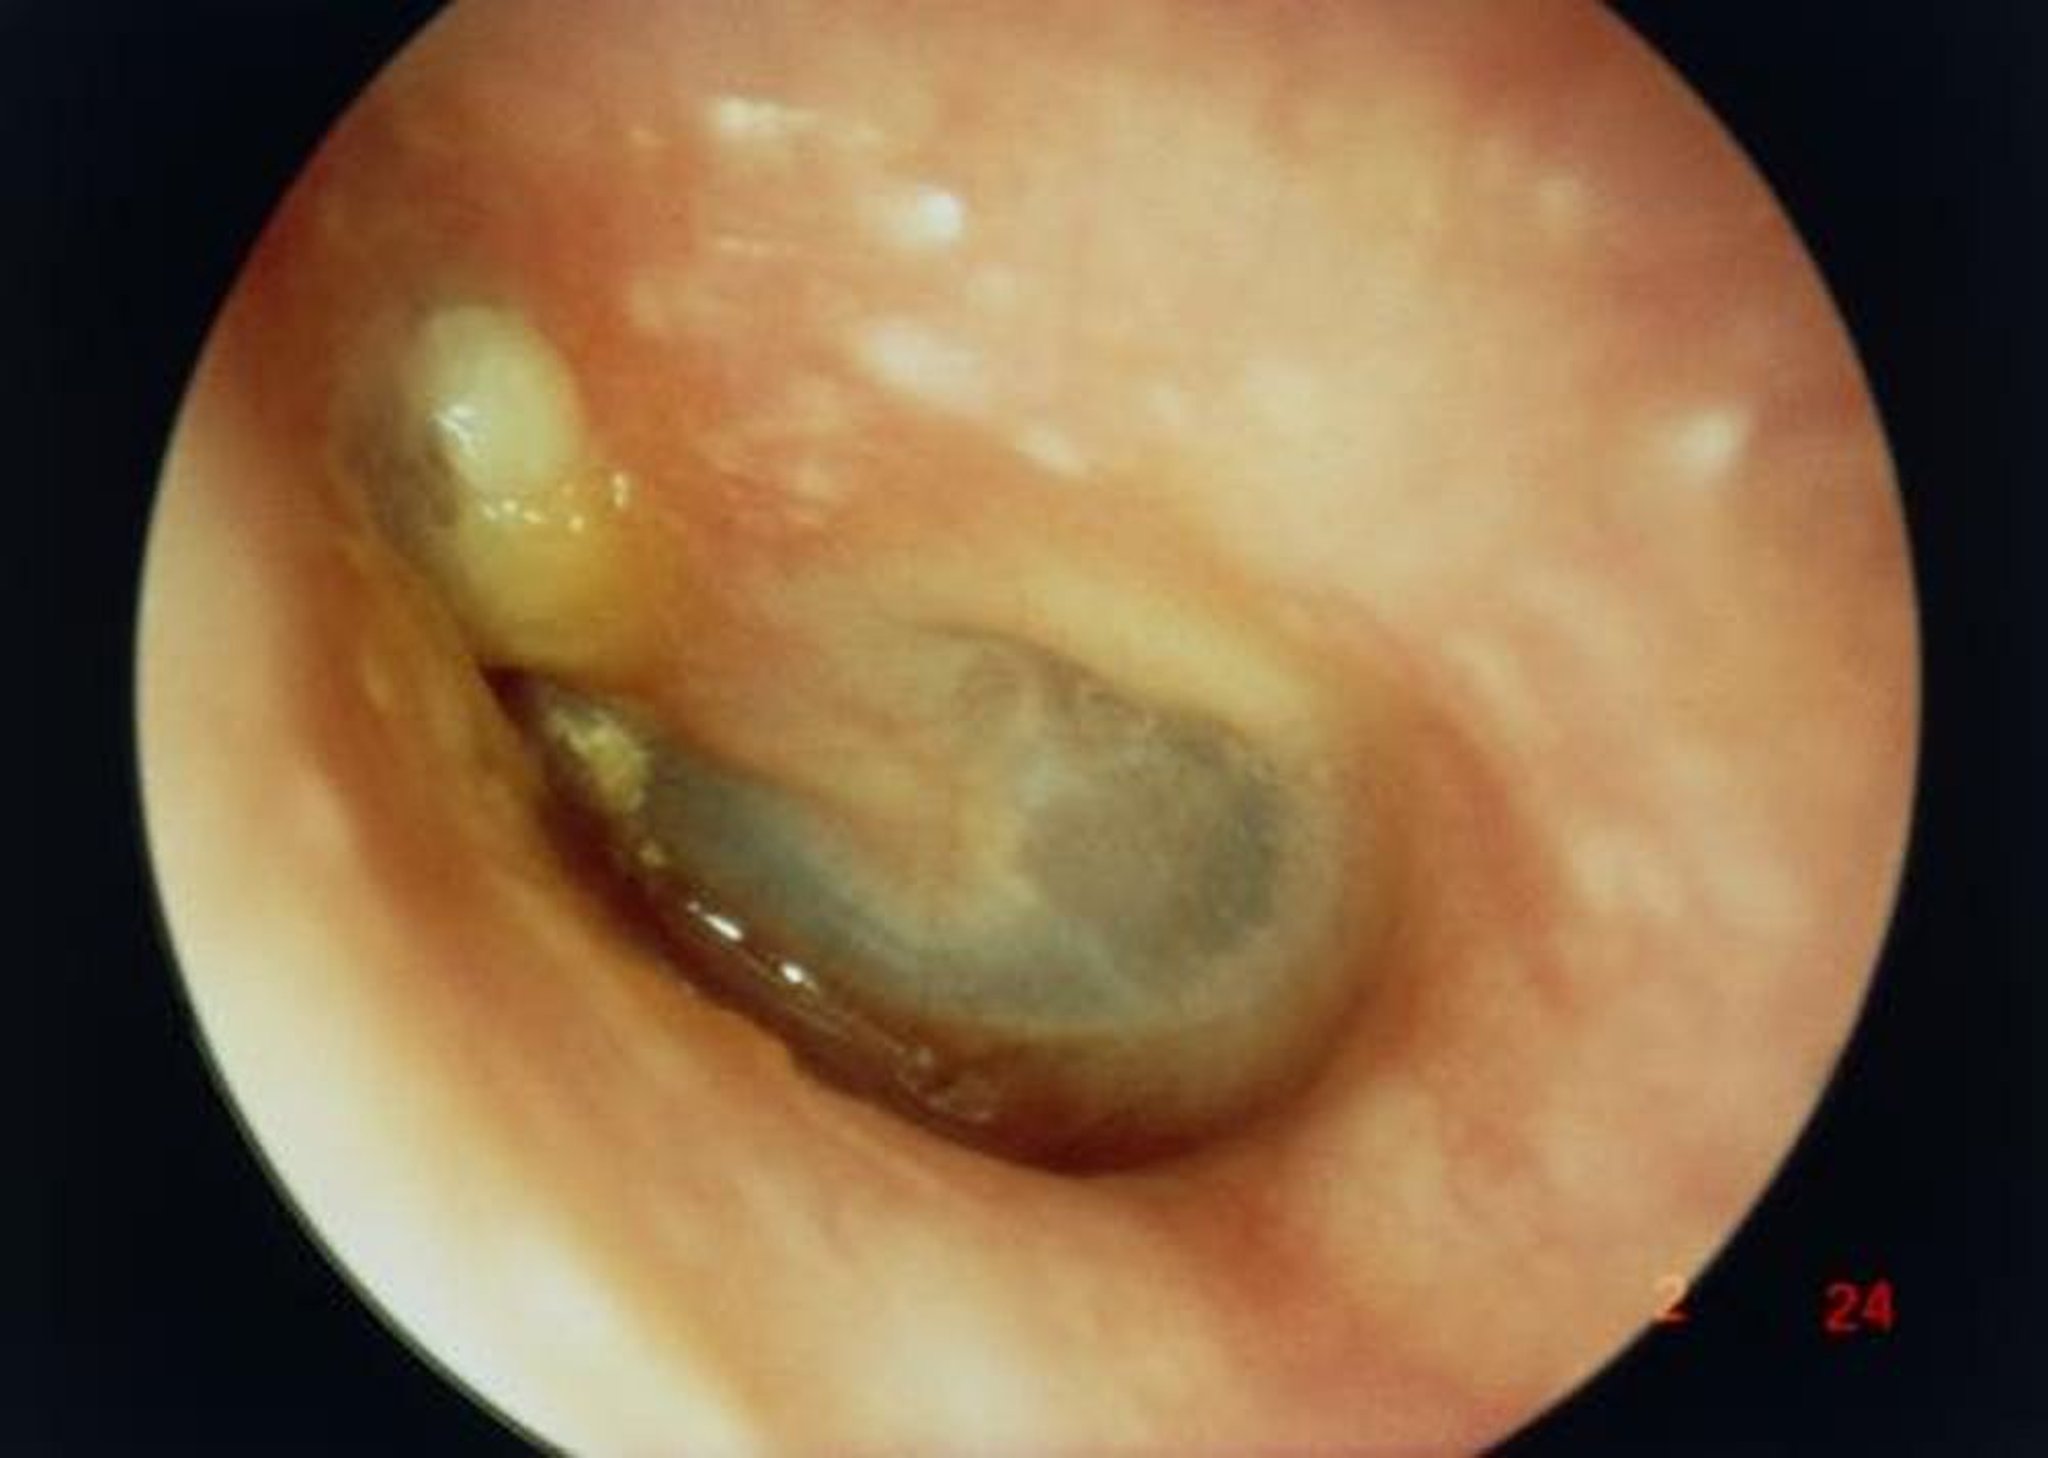

Nesta imagem, a incidência ao longo do meato acústico externo mostra um grande colesteatoma (massa branca à esquerda superior ao processo curto do martelo), resultando em uma perfuração da membrana timpânica.

PROFESSOR TONY WRIGHT, INSTITUTE OF LARYNGOLOGY & OTOLOGY/SCIENCE PHOTO LIBRARY